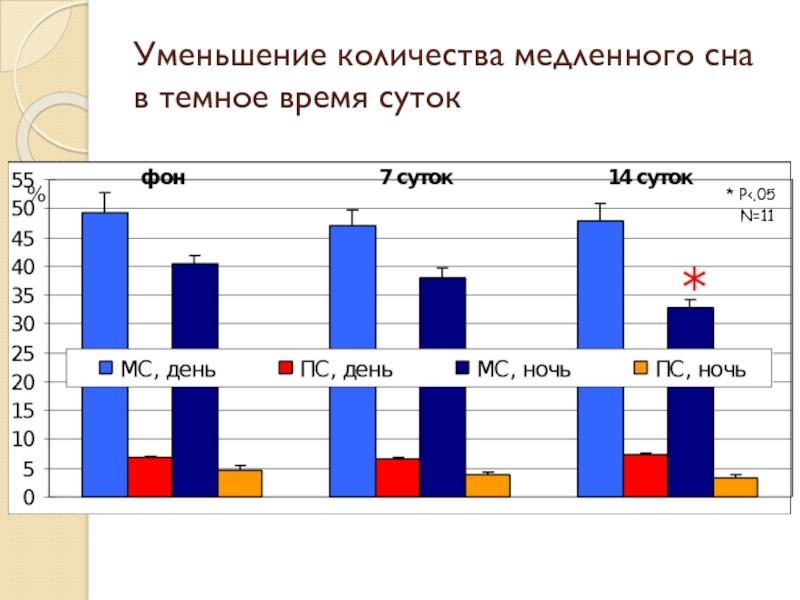

- 18. Уменьшение количества медленного сна в темное время суток * P

Слайд 20Результаты

Обнаружено уменьшение количества медленного сна и увеличение двигательной активности в темное время суток на 14-ый день после введения МФТП

Обнаружено уменьшение количества медленного сна и увеличение двигательной активности в темное время суток на 14-ый день после введения МФТП